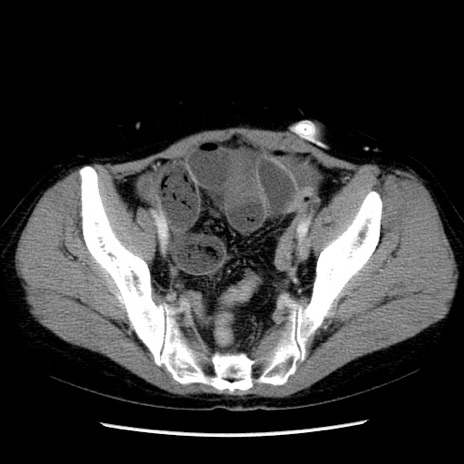

冠状断像